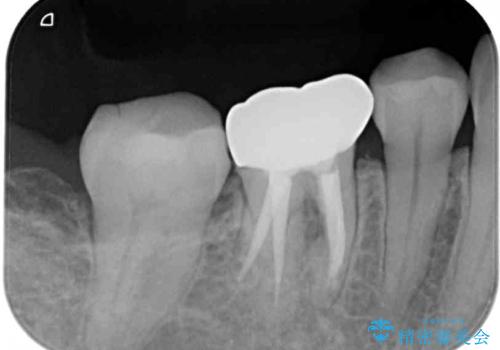

初診から2年以上が経過していますが、排膿路が再発することはなく、良好な状態を保っています。